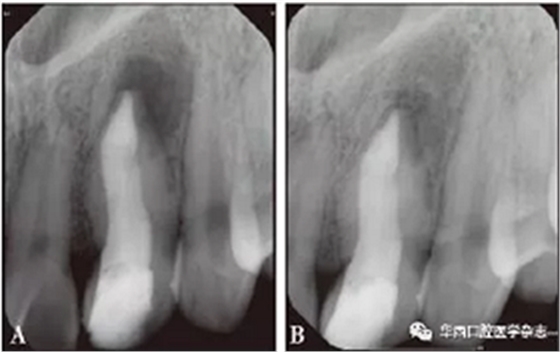

因患者出國(guó)未歸,根尖屏障術(shù)后3個(gè)月(2017年7月24日)回國(guó)復(fù)診自述無(wú)不適,叩診陰性,冠方充填物完整無(wú)脫落,X線片示根尖區(qū)低密度透射影像有縮小跡象(圖3A)??紤]患牙管腔過(guò)大,管壁過(guò)薄,容易發(fā)生牙折,與修復(fù)科醫(yī)生會(huì)診,擬行纖維樁加固術(shù),橡皮障隔離術(shù)區(qū),去除原充填物后顯微鏡下可見(jiàn)iRoot BP Plus固化完全,上端熱牙膠充填3 mm,2根25號(hào)纖維樁體置入根管粘接固位(圖3B),冠部樹(shù)脂修復(fù)(圖3C、3D),攝X線片(圖4A)。

A:術(shù)后3個(gè)月;B:術(shù)后1年。

圖 4 術(shù)后根尖片

根尖屏障術(shù)后1年(2018年3月21日)復(fù)診攝X線片,患牙根尖區(qū)低密度透射影像明顯縮小,根尖區(qū)趨于愈合(圖4B)。